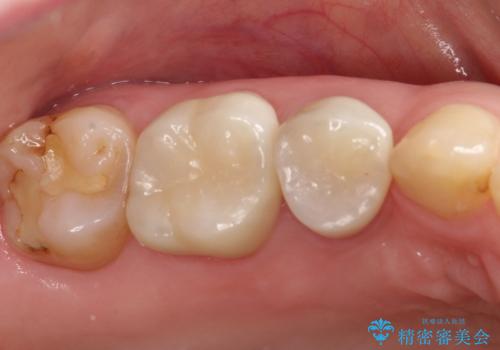

むし歯の治療。ゴールドインレーによる修復

- 定期健診にてむし歯を認めたためゴールドインレーにて治療を行いました。

ゴールドインレーは適合が良く、割れることもないため、長期的に安定した治療法となります。